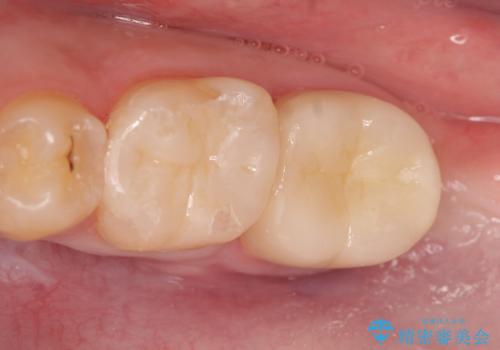

セラミックインレー 下の一番奥歯 歯ぐきの厚みを減らしてぴったりに入れます(ディスタルウェッジ+骨外科)

一番奥歯の後ろに虫歯が 処置の難しい虫歯